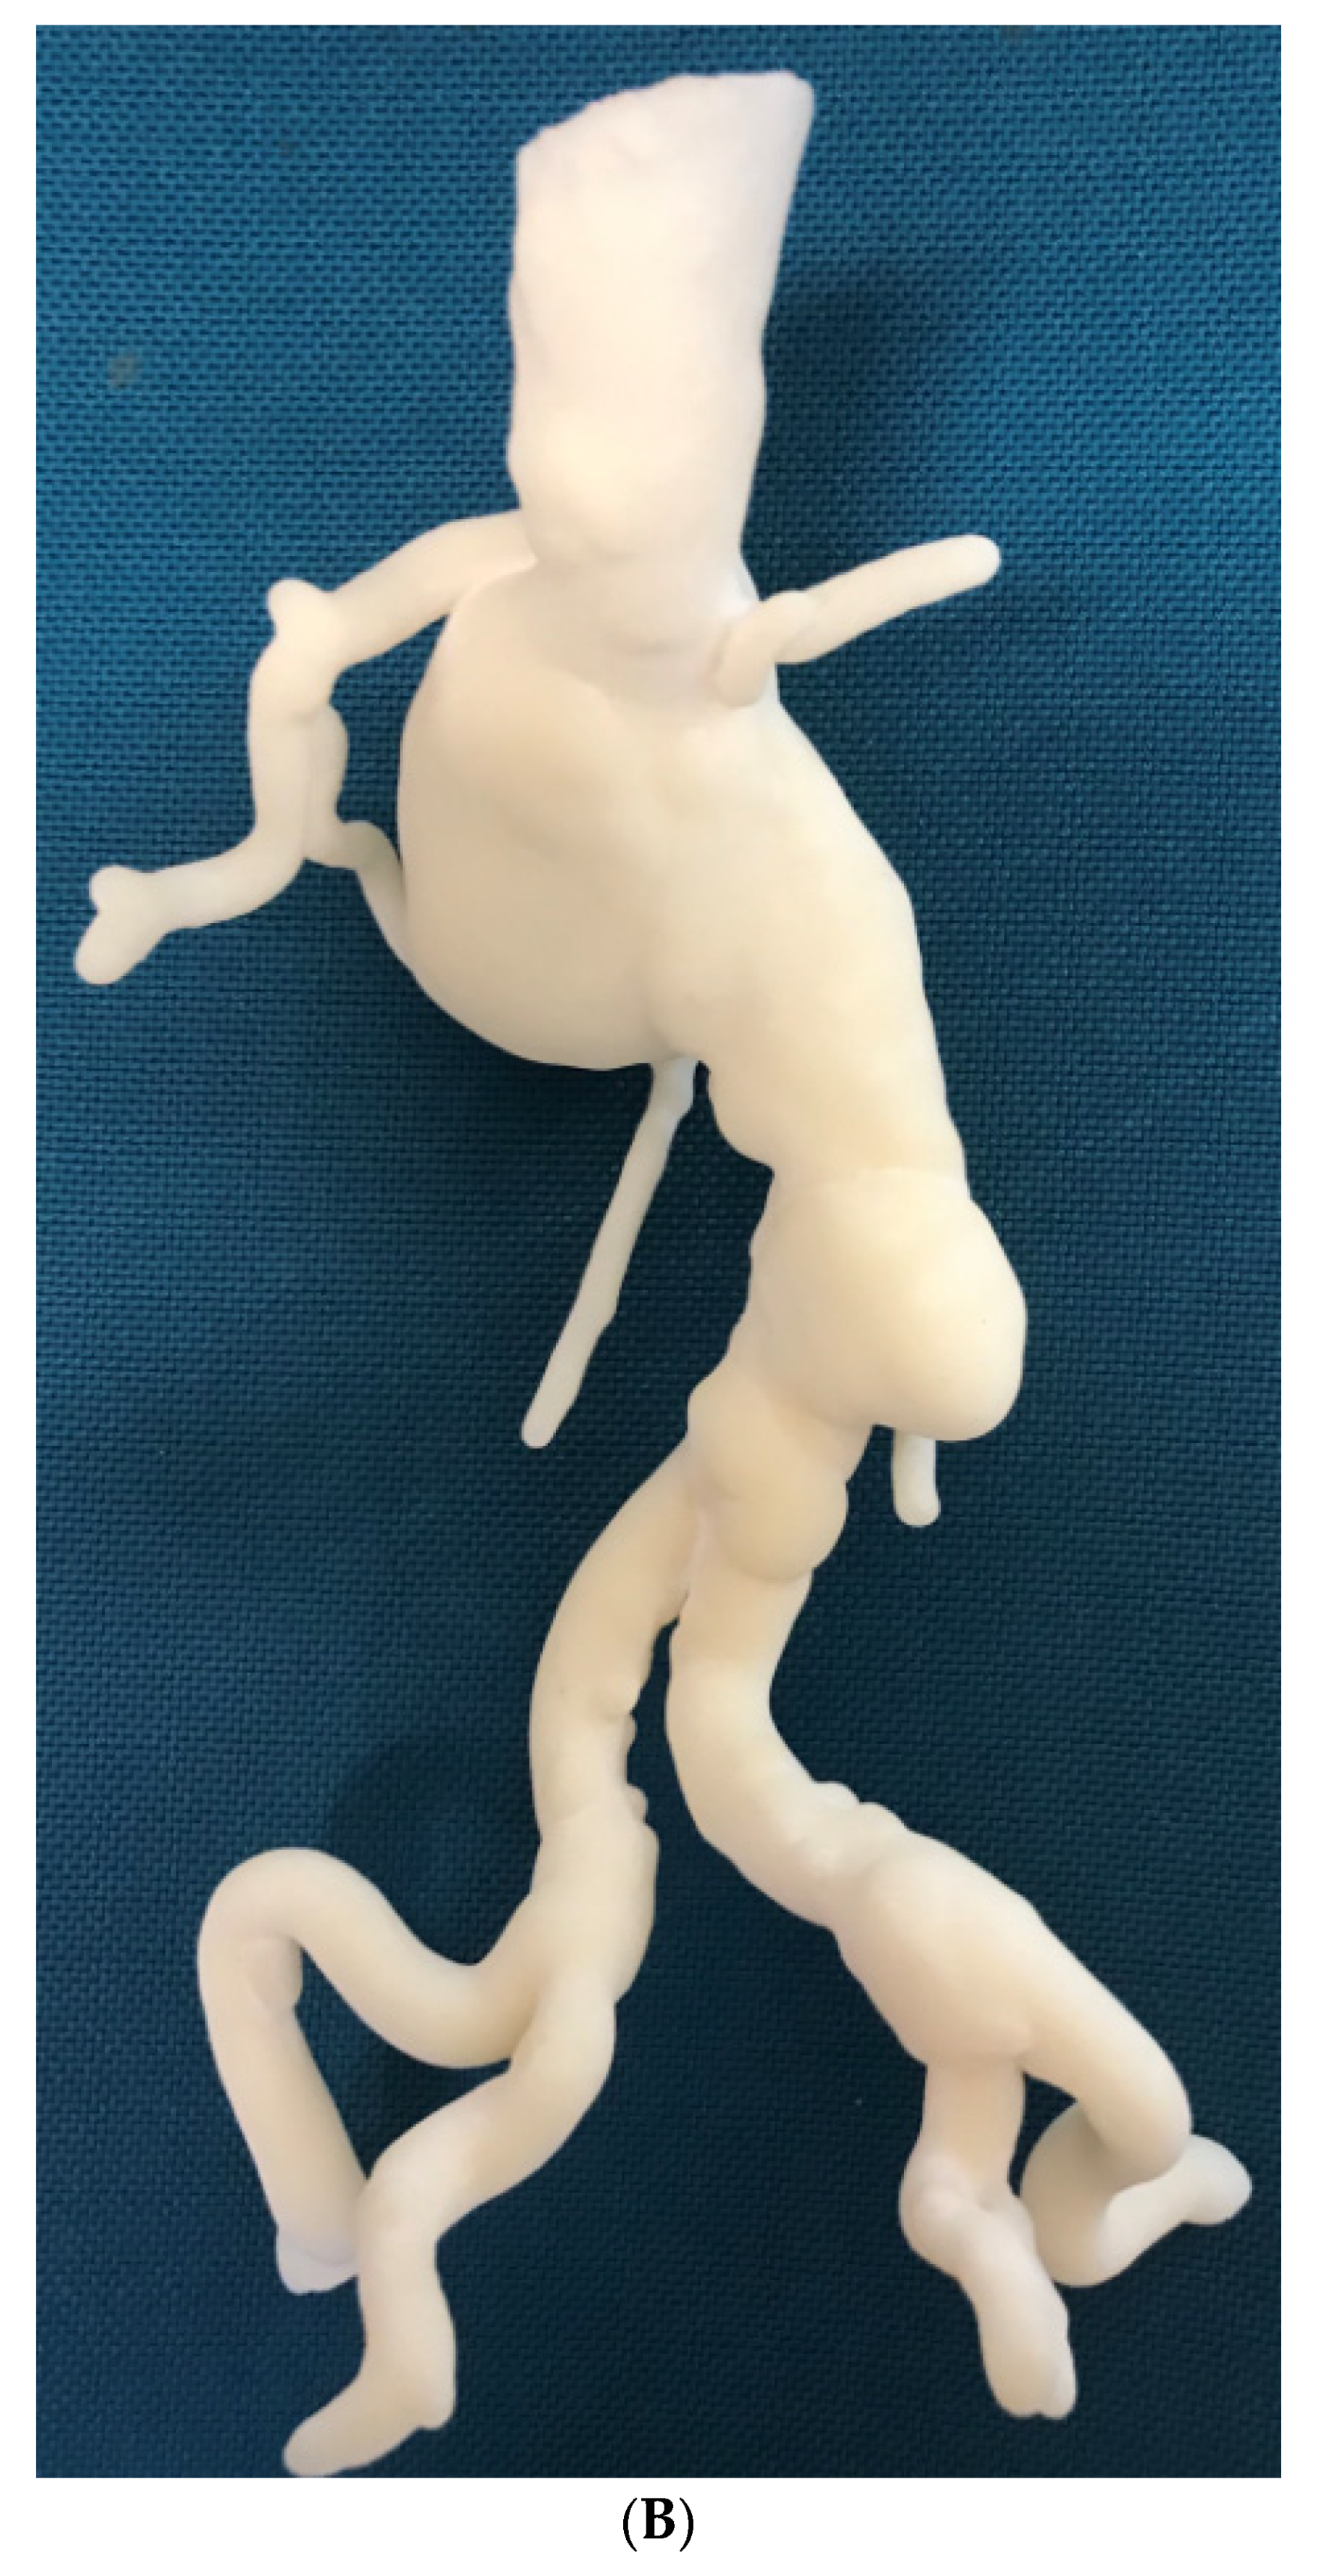

3.4. 3D Printing in Aortic Aneurysm and Aortic Dissection

- Ho, D.; Squelch, A.; Sun, Z. Modelling of aortic aneurysm and aortic dissection through 3D printing. J. Med. Radiat. Sci. 2017, 64, 10–17. [Google Scholar] [CrossRef] [PubMed]

- Sun, Z.; Squelch, A. Patient-specific 3D printed models of aortic aneurysm and aortic dissection. J. Med. Imaging Health Inf. 2017, 7, 886–889. [Google Scholar] [CrossRef]